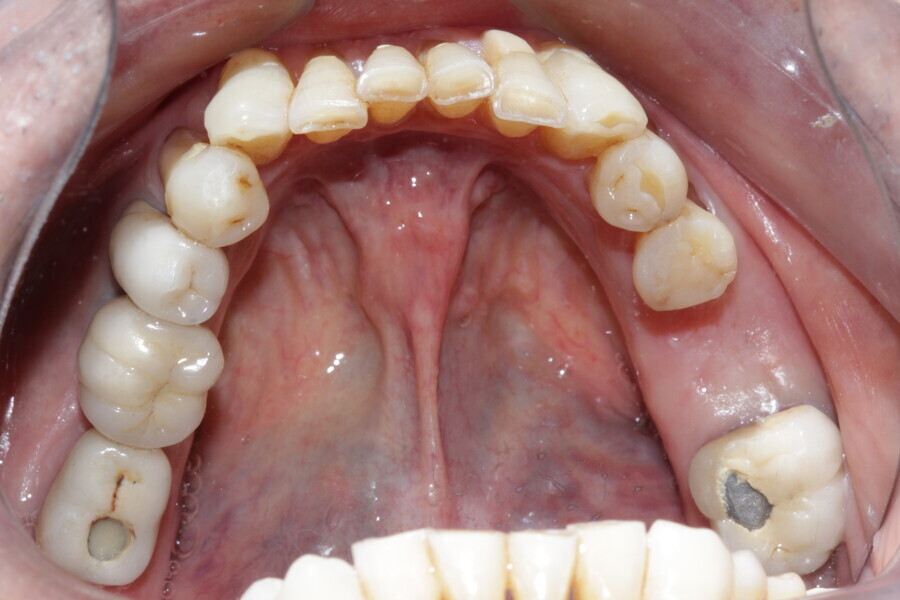

Figure 6 Maxillary occlusal view before treatment